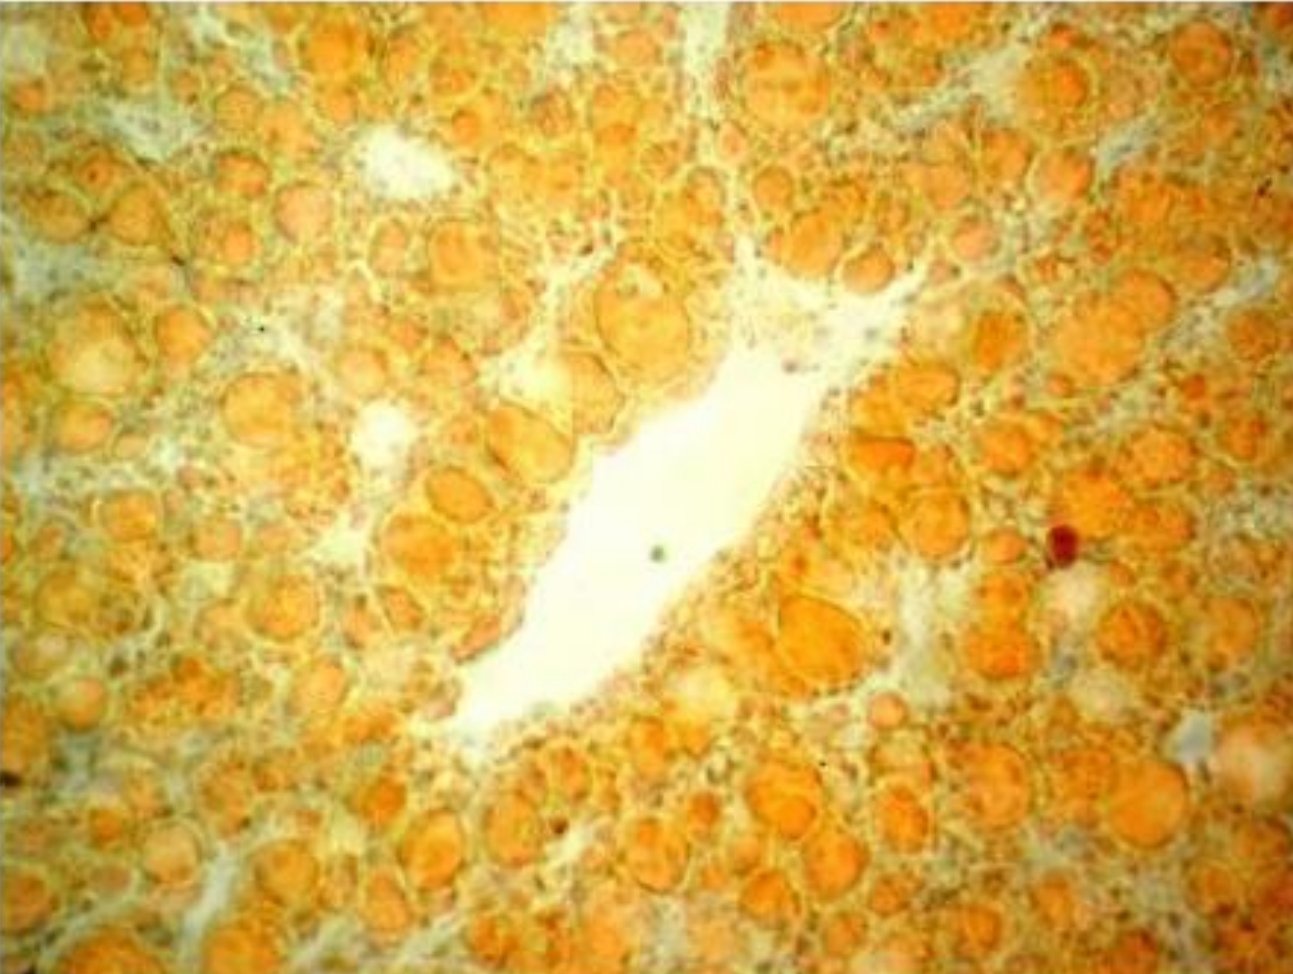

1. Sudan 3

2. Transverse section of ai1ery

3. Deposition of fats can be seen in orange color in the intima. Vessel is narrowed.

4. Atherosclerosis of artery (2nd stage lipidosis)

5. Disbolism of lipids and its esters, hyperlipidemia, increased permeability ofintima destruction of endothelium, hype11ension